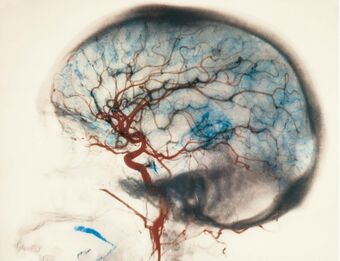

Enfermedades Vasculares del Cerebro

Isquemia y Hemorragia Cerebral. Las Malformaciones Vasculares Imagen de la irrigación cerebral La irrigación cerebral corresponde al flujo de sangre que llega al cerebro a través de una compleja red de arterias y venas. Las arterias transportan sangre ...